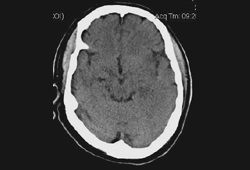

TC de crânio sem contraste de um paciente com encefalite por HSV: mostra hipodensidades sutis envolvendo a região insular esquerda. Algum turvamento das margens cinzas-brancas e apagamento dos sulcos na região temporal esquerda são detectáveis

Do acervo pessoal de Catalina C. Ionita, MD; usado com permissão